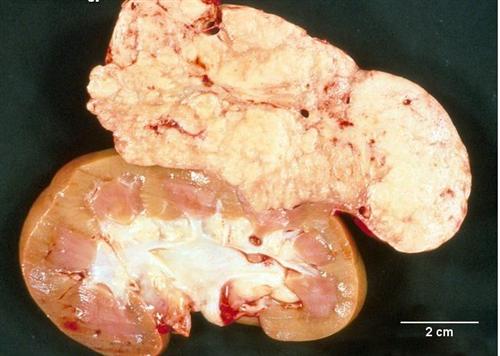

相关图片